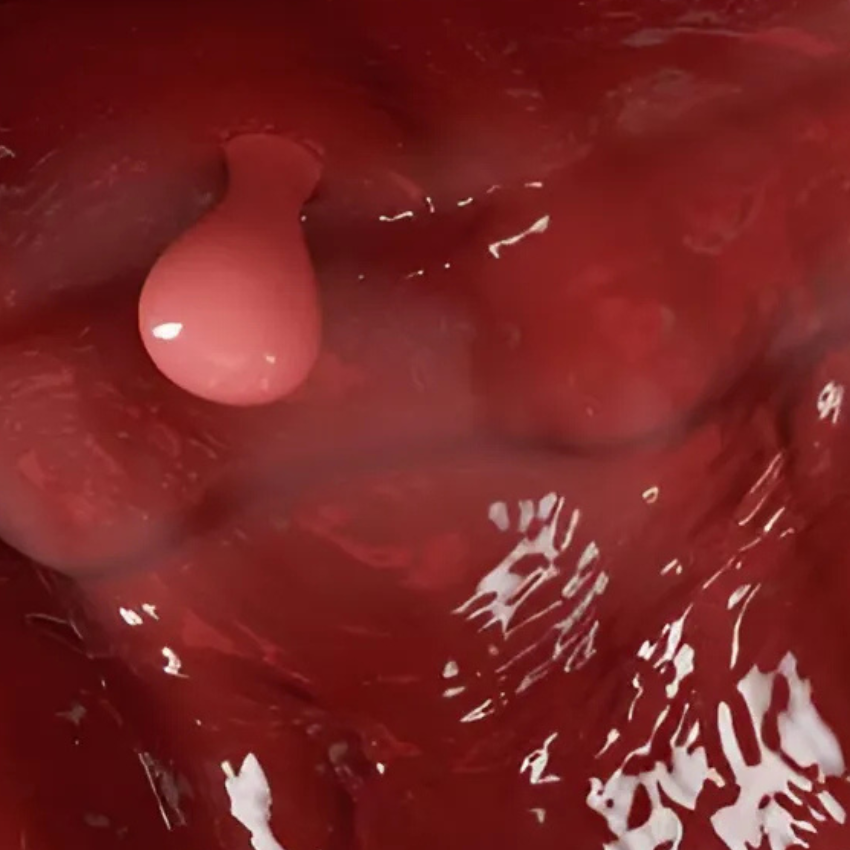

Imágenes de pólipos endometriales

Es el método más preciso. Permite visualizar directamente el interior del útero con una cámara de alta definición e incluso tomar una biopsia o remover el pólipo en el mismo procedimiento. Es mínimamente invasiva.

La detección precisa con histeroscopía permite identificar y extirpar pólipos rápidamente, reduciendo las molestias y optimizando tu perfil reproductivo con mínima intervención y recuperación rápida.